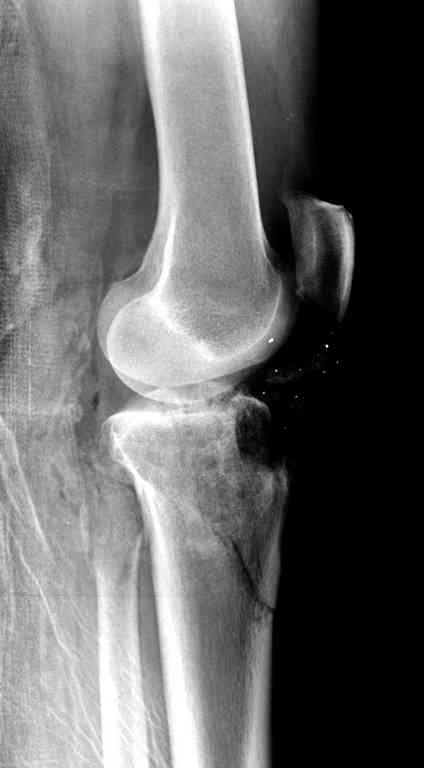

Все ипсилатеральные переломы относятся к категории нестабильных, и лечение их бывает сложным из-за двойного перелома вокруг сустава (floating joint). Основная тактика состоит в проведении поэтапного лечения с окончательной фиксацией cуставной поверхности.

На первом этапе с задачей справляется наружный фиксатор, который создает благоприятные условия для закрытия ран и контролирует длину конечности. На данном этапе рекомендована КТ, чтобы увидеть топографию фрагментов для расчета направления фиксирующих элементов.

Одинокий кортикальный шуруп не удержит тибиальный бугор, сустав тибиал плато оставлен без репозиции и фиксации.

Здесь применение материала Plexur http://www.plexur.com для пластики при дефектах кости у больной с огнестрельной раной латерального тибиал плато с повреждением малоберцового нерва. Несмотря на интактный медиальный мышелок, для профилактики от вальгуса установлен АВФ и сделана ангиограмма.